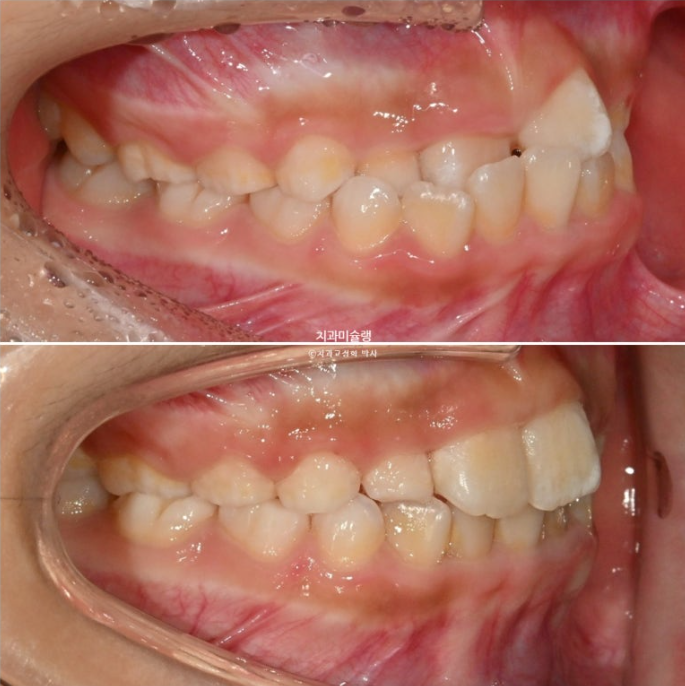

앞니가 거꾸로 물려서 온 7세 어린이 입니다.

윗니가 전체적으로 아랫니와 거꾸로 물리는 반대교합 입니다.

공간부족으로 앞니가 덧니처럼 나왔습니다.

두달 후 앞니 반대교합이 해소가 되어 왔습니다.

25.06

덧니처럼 배열에서 벗어나있던 앞니가 꽤 제자리로 들어온 것이 보이죠?

전 후 비교 보겠습니다.

25.04~25.09